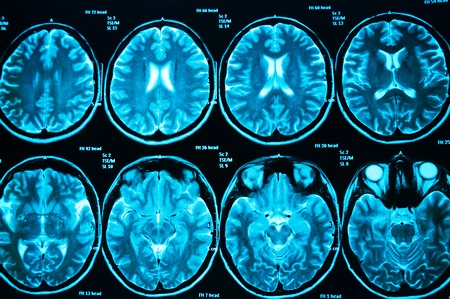

Если больной онкологией, ощущает на себе признаки наличия опухолей в головном мозге, он должен пойти к своему врачу и рассказать об ухудшении состояния. Лечащий врач назначит дополнительную диагностику, которая позволит определить, не попали ли метастазы в головной мозг. В данном случае больной проходит:

- КТ и МРТ;

- патопсихологическое обследование (определение речевых проблем и умственных) – проводится в дальнейшем регулярно с целью выявить ухудшение состояния больного;

- нейроофтальмологическую диагностику;

- неврологическое обследование;

- электроэнцефалографию;

- лабораторный анализ ликвора и прочие.